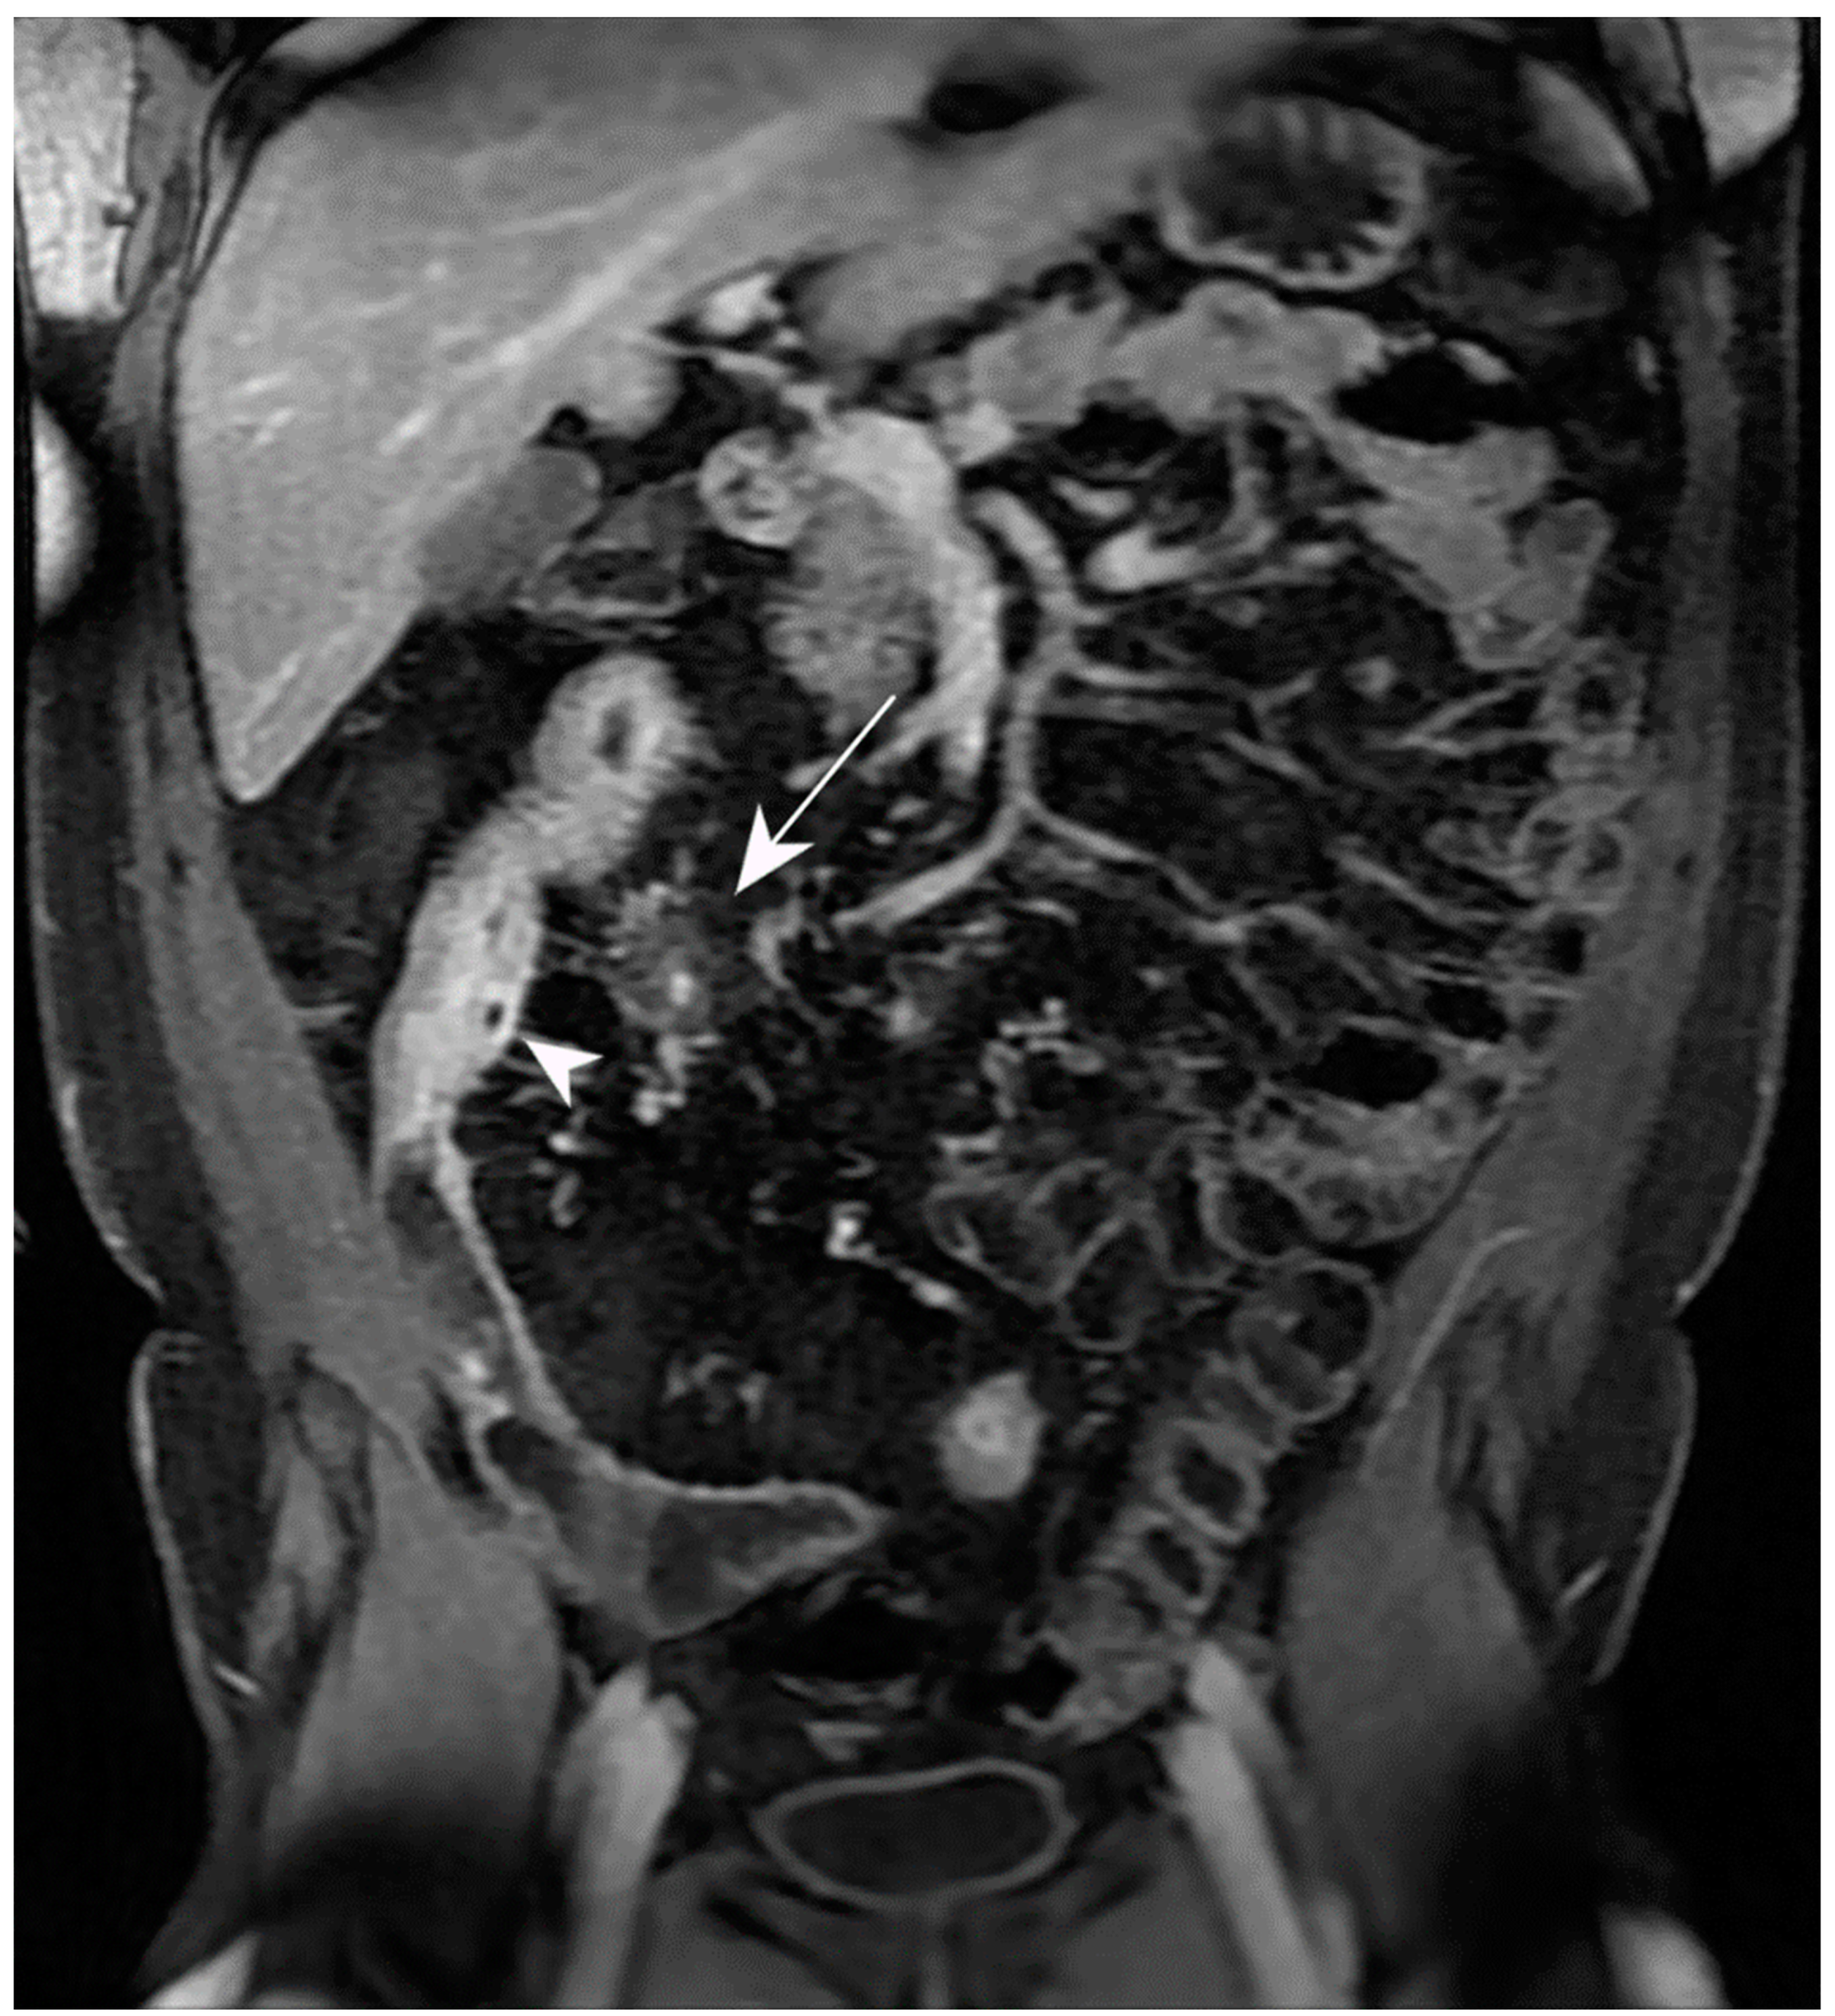

5.3. Fistulising/Perforating Subtype